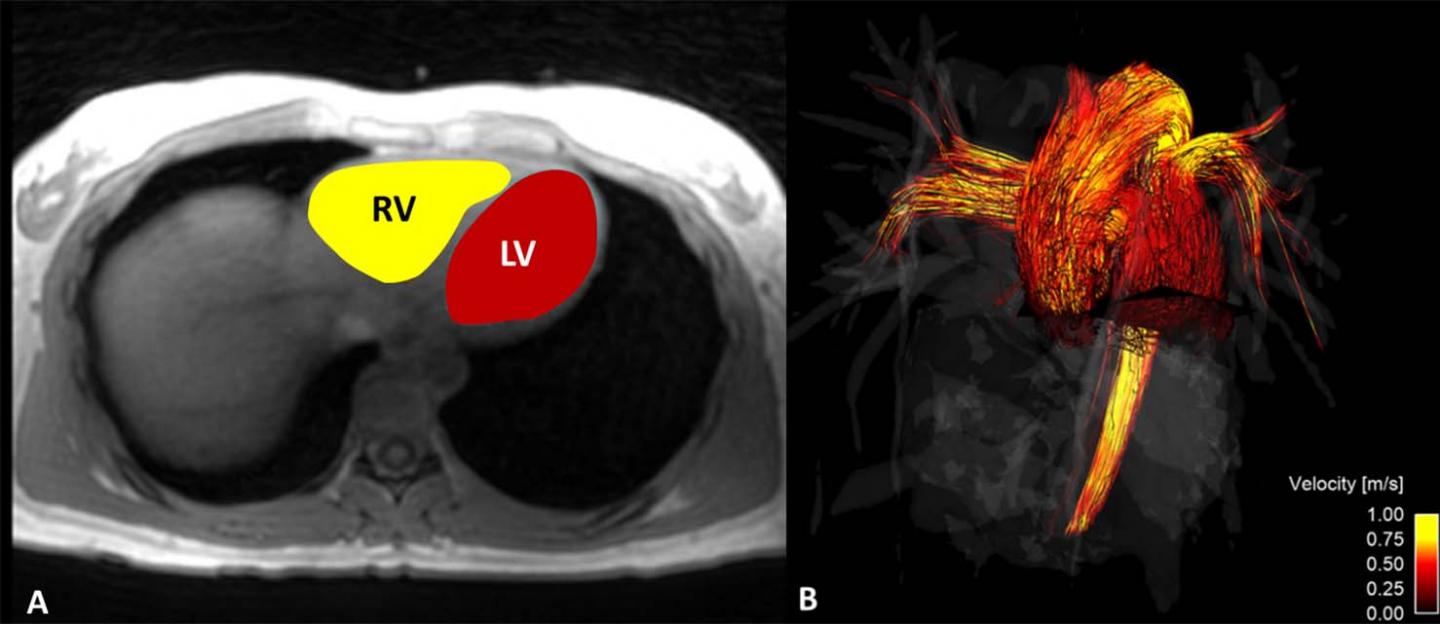

image: Four-dimensional (4D) flow MRI was used to calculate, A, kinetic energy in the right ventricle (RV) and left ventricle (LV). Time-averaged 4D flow MRI magnitude data were used to segment the RV and LV and, B, flow through the main pulmonary artery and ascending aorta.

For the new study, researchers used a sophisticated imaging technique called 4D flow MRI to study gender differences in the left ventricle, the heart's main pumping chamber. They derived various blood flow parameters from MRI scans obtained from 20 men and 19 women and correlated them with cardiac function.

The data showed some significant differences between the genders. Kinetic energy, which is one indicator of energy expenditure during contraction and filling of the heart, was significantly higher in the left ventricles of men. Vorticity, a measure of regions of rotating flow that form during different points of the cardiac cycle, was higher in women, as was strain, a measure of left ventricular function.